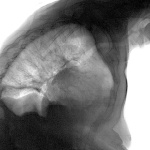

Ну чё задне-нижние -то отделы на боковой "срезаны"? Если Вас смущает правый корень, то это-лёгочная артерия.

Шаровидная тень в средней доле справа. Динамики нет >> доброкачественный процесс. С учётом возраста, доживет без нашей помощи. Оставила бы в покое.

Лёгочная. На мой взгляд.

NIL, смотрите, -левая такая же. Ну как аргумент.

А что с левым куполом диафрагмы? Это что - обызвествление? Или как это называется?

Гипертензию лёгочную бы заключил. И адентию припомнил.;) На боковом бабушка выпала из кадра!.. Надеюсь, на ногах всё ж устояла.))